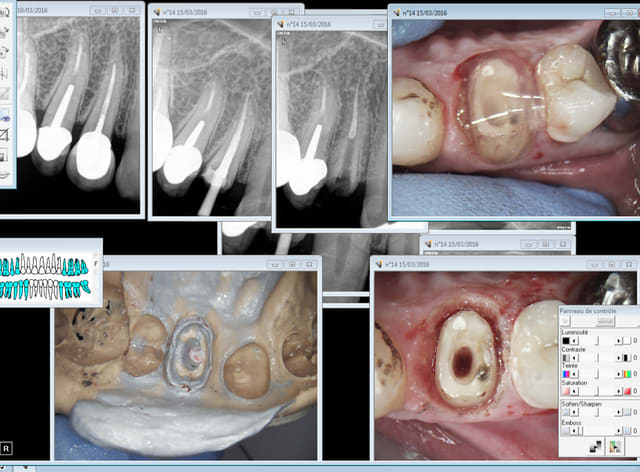

illustration RTE 14 ( arthrite infectieuse pas visible radio) taille empreinte dans la séance ( ic provisoire) 1H.

Capture d e cran 2016 03 15 10.07 - Eugenol